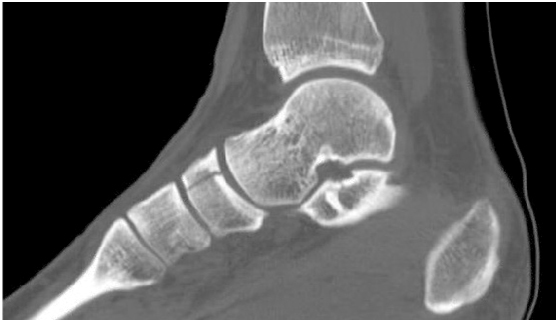

The most common method used to confirm a stress fracture is an X-ray of the affected segement. A stress fracture can sometimes not been seen on regular x-rays or fail to appear after the initial few weeks of pain. Hence, a computed tomography (CT) scan or magnetic imaging (MRI) will be ordered instead.